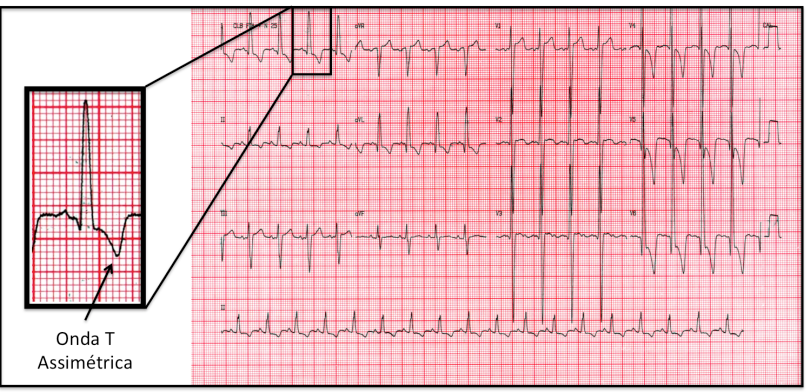

A onda T representa, no eletrocardiograma, a repolarização ventricular. Geralmente o registro é de uma deflexão arredondada e lenta, habitualmente com polaridade igual a do complexo QRS. Normalmente, a onda T é assimétrica, com ramo ascendente lento e descendente com maior inclinação.

DICA: quando a onda T invertida for simétrica, ou seja, a parte descendente e ascendente tiverem duração similares, pensar em coronariopatia como causa. Já se a onda T for assimétrica (parte descendente mais lenta do que a parte ascendente), pensar em outras etiologias.

Paciente com sobrecarga de ventrículo esquerdo: